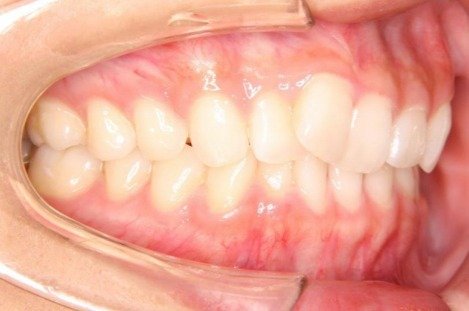

掲載症例について:

患者】 10代女性

【主訴】 前歯のガタガタ

【診断】 過蓋咬合を伴う叢生

【抜歯の有無】 非抜歯

【治療期間】1年8ヶ月 通院回数12回

【治療内容】親知らずを抜歯した後、マウスピース型カスタムメイド矯正歯科装置(製品名インビザライン 完成物薬機法対象外)を使用して主訴である叢生および過蓋咬合の改善を行いました。

【費用】88万(税込)

【リスク】矯正歯科装置を付けた後しばらくは違和感、不快感、痛みなどが生じることがあります。

矯正中は矯正歯科装置が歯の表面についているため食物が溜まりやすく、また歯が磨きにくくなるため、虫歯や歯周病が生じるリスクがあります。

歯を動かすことにより歯根が吸収して短くなることや歯肉がやせて下がることがあります。

矯正歯科治療は公的健康保健の適応外の自費治療(自由診療)となります。